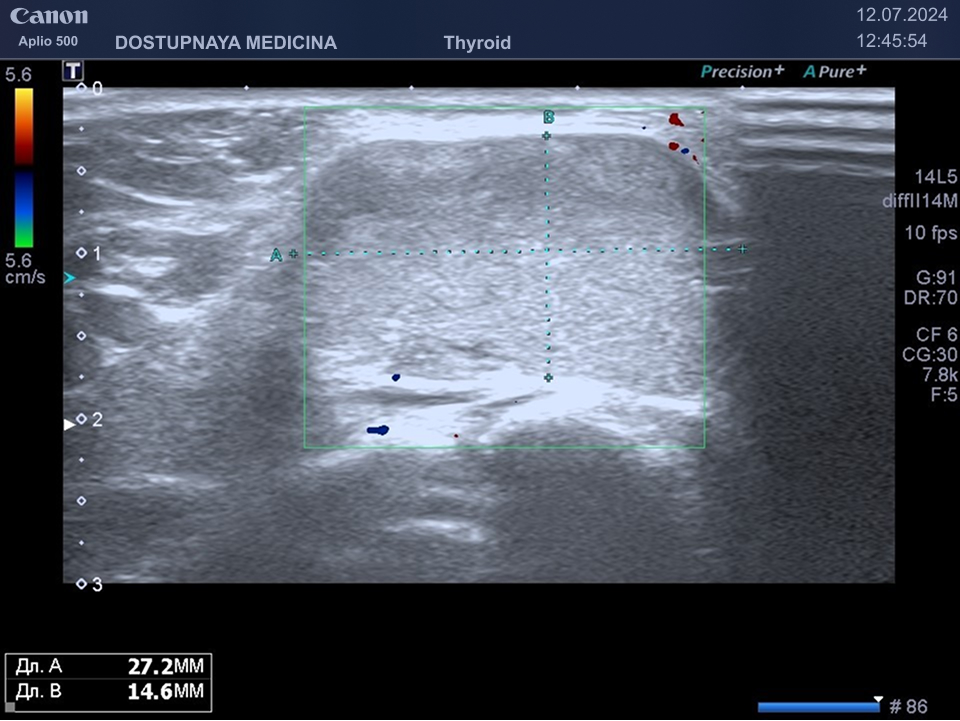

При ультразвуковом исследовании важно разобраться имеем мы дело с лимфаденопатией по воспалительному типу или с лимфаденопатией по пролиферативному типу. При лимфаденопатии по воспалительному типу сохраняется дифференцировка лимфоузла на слои, но корковый слой лимфатического узла утолщен, кровоток в лимфоузле хиларный (центральный), чаще всего отмечается усиление хиларного кровотока в режиме ЦДК, узел имеет овоидную форму и его горизонтальный размер всегда больше вертикального.

При лимфаденопатии по пролиферативному типу лимфоузел приобретает округлую форму и увеличивается в размерах, горизонтальный его размер становится равным вертикальному, кровоток перестаёт быть центральным и становится хаотичным, дифференцировка лимфоузла на слои отсутствует.